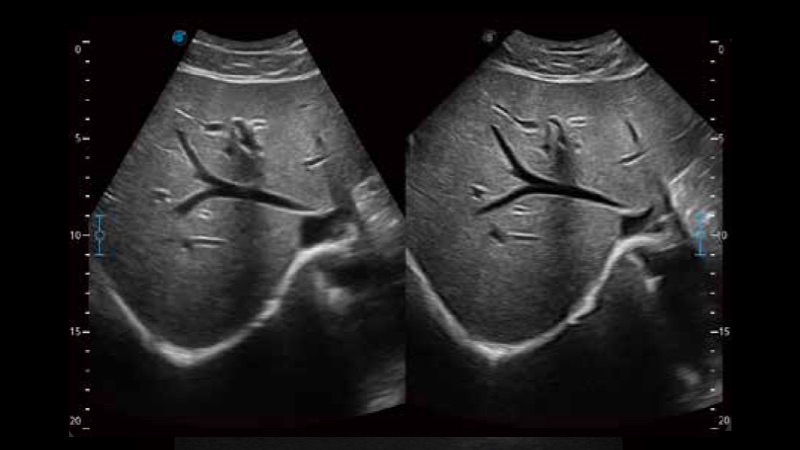

開立醫(yī)療通過不斷的技術(shù)創(chuàng)新,為大眾的生命健康提供持續(xù)關(guān)愛。P12 Plus采用全新一代超聲成像平臺(tái),新平臺(tái)旨在將真實(shí)還原組織解剖結(jié)構(gòu)作為首要目標(biāo)。平臺(tái)采用全新集成化硬件模塊,搭載新一代芯片,系統(tǒng)性能得到大幅提升,為您的診斷提供了豐富的臨床信息。優(yōu)異的圖像表現(xiàn),豐富的探頭配置,全面的應(yīng)用功能,為您日常診斷提供了可靠的助手。

彩色多普勒超聲診斷系統(tǒng)